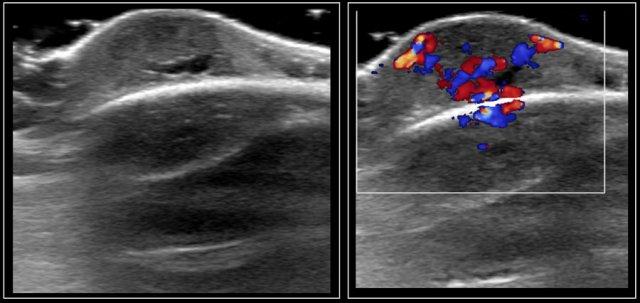

Trên siêu âm, u vôi hóa biểu mô lành tính (pilomatrixoma) biểu hiện là một khối u hình bầu dục nằm giữa lớp bì và lớp dưới da.

Khối u tăng âm, đôi khi có vôi hóa và bóng lưng âm.

Thành khối thường giảm âm và trên Doppler màu có thể thấy các mạch máu nhỏ trong thành.

Những hình ảnh này là của một khối u chắc ở cổ của một cô gái 17 tuổi.

Kết quả lấy mẫu tế bào học không có kết luận rõ ràng.

Siêu âm cho thấy hình ảnh điển hình của u vôi hóa biểu mô lành tính (pilomatrixoma), được xác nhận bằng giải phẫu bệnh sau khi cắt bỏ.

Some perfusion in the wall of the pilomatrixoma is seen.